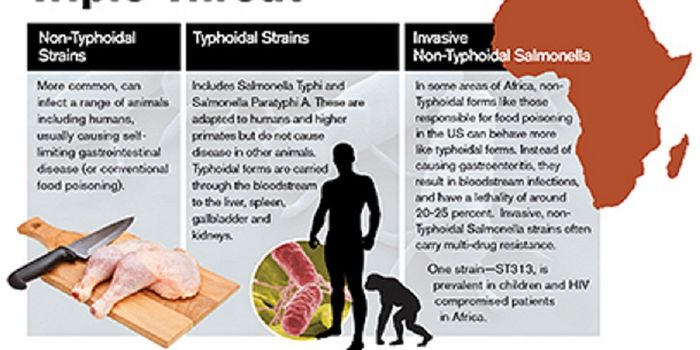

SEP 13, 2015MicrobiologySalmonella enterica are a group of rod shaped bacteria that are most commonly associated with foodborne illness in human ...